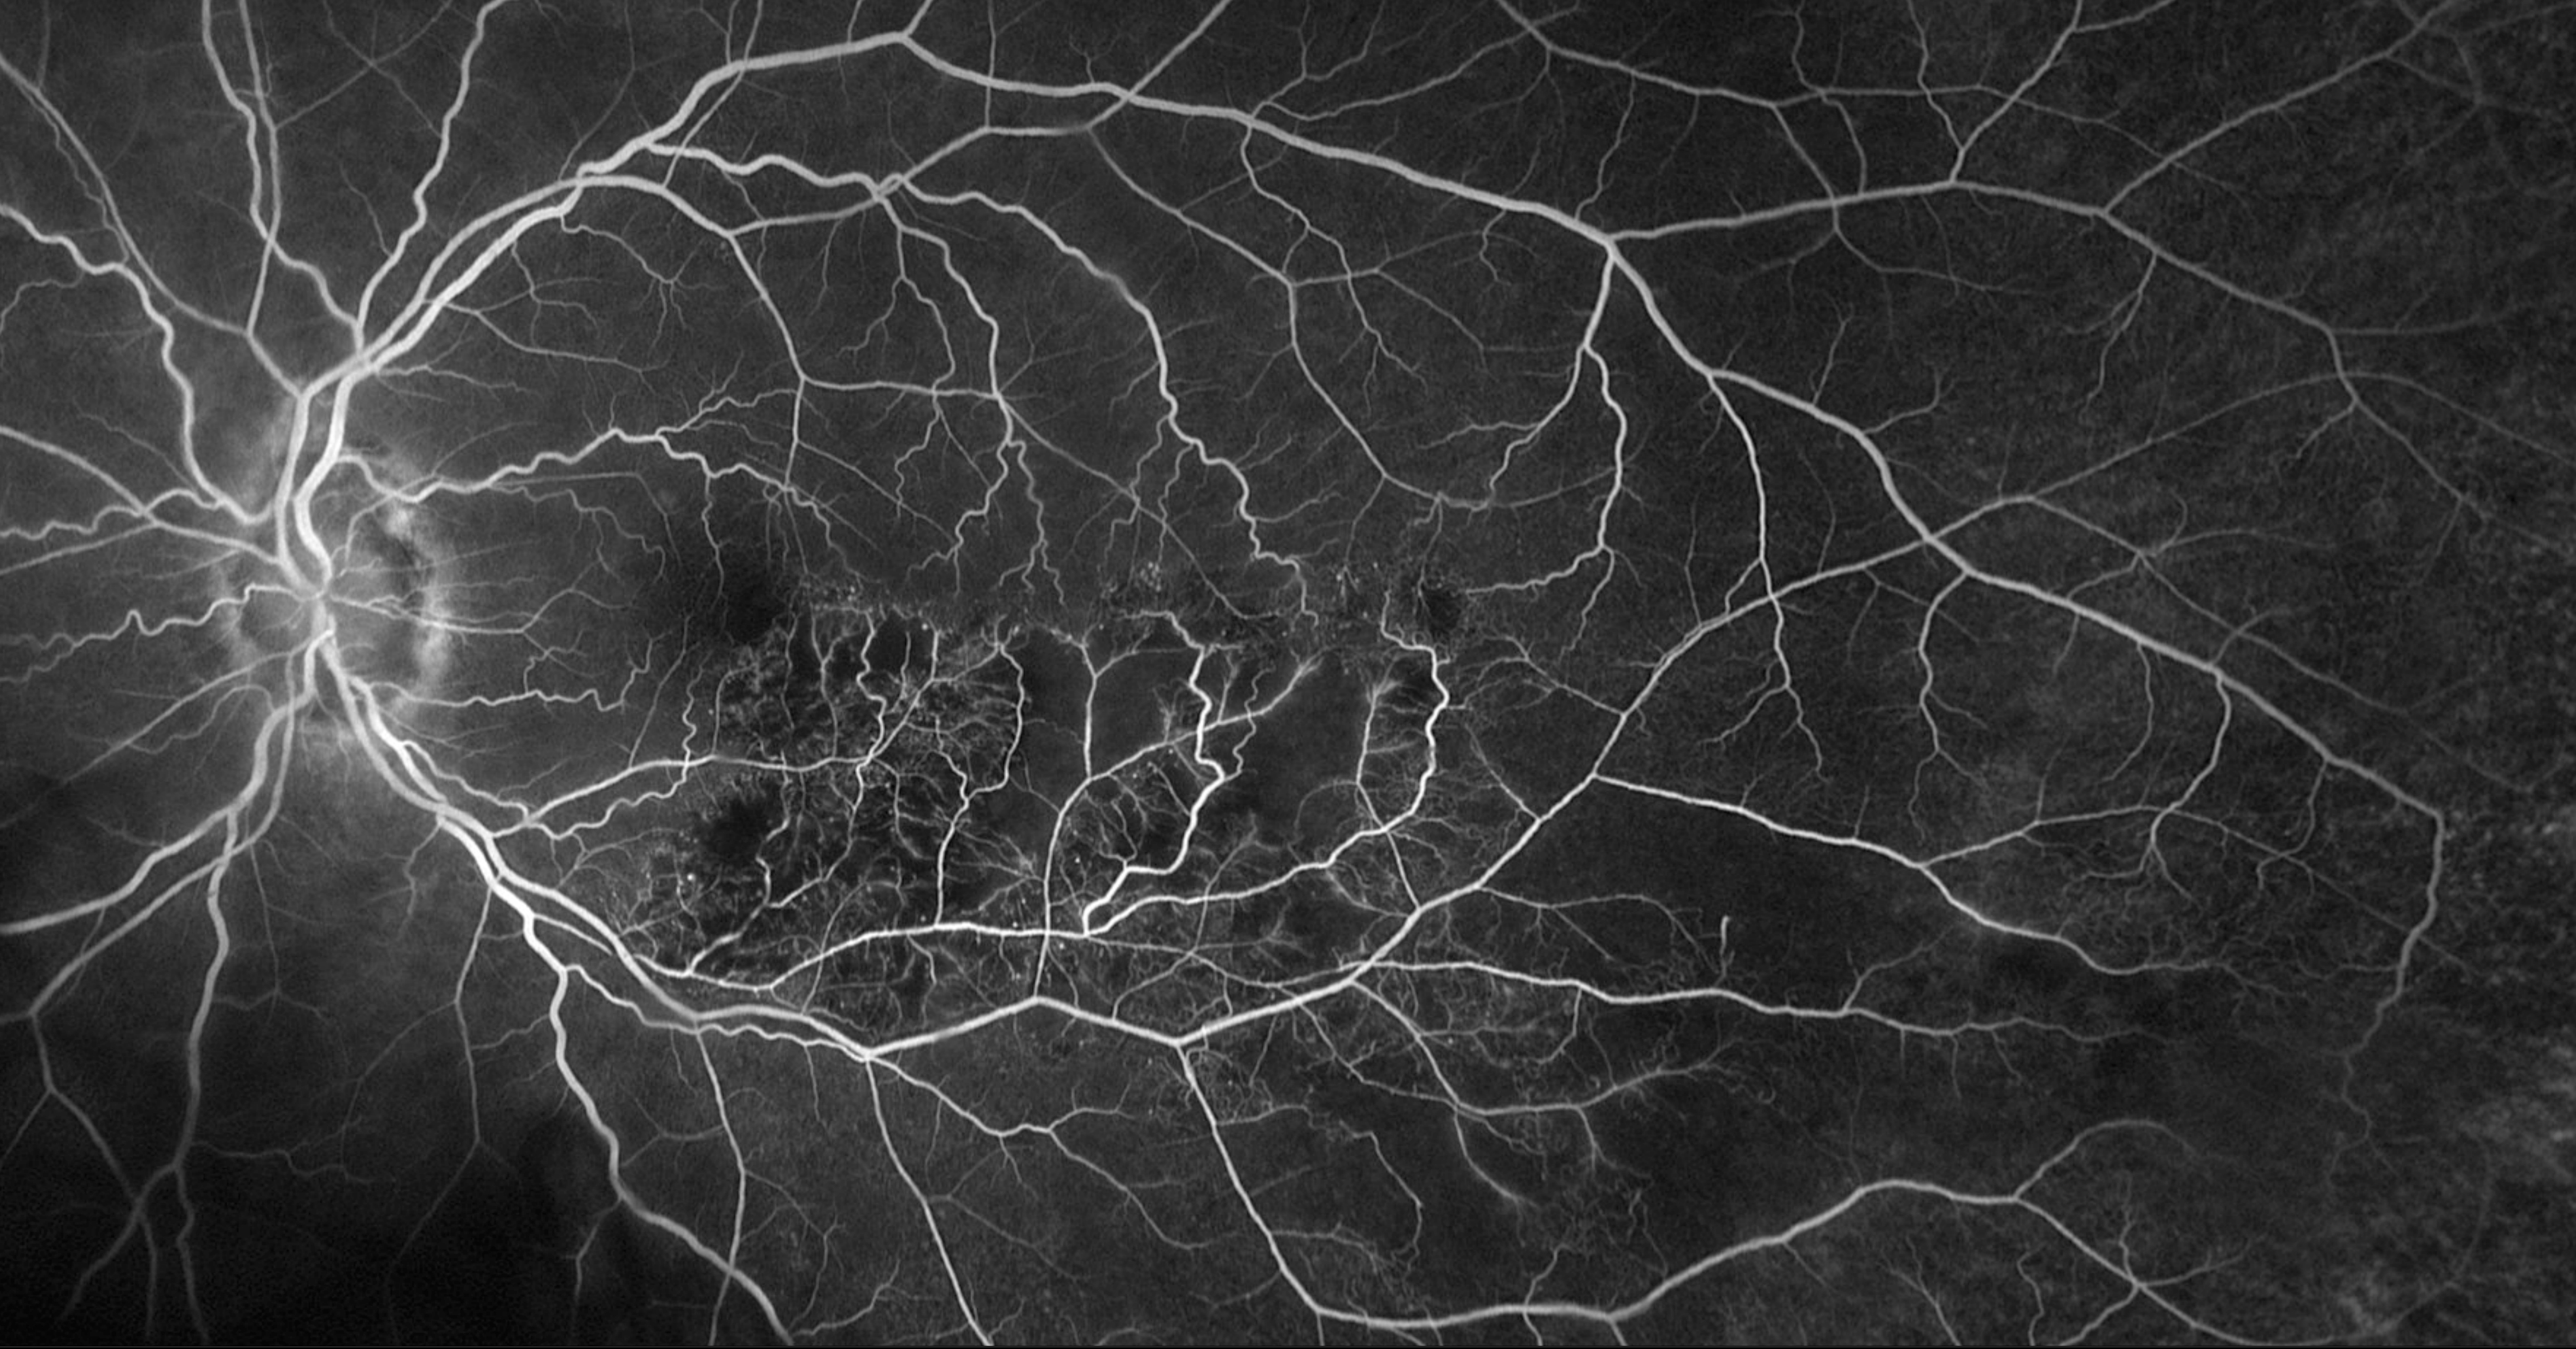

Learn about retinal diseases and conditions we treat